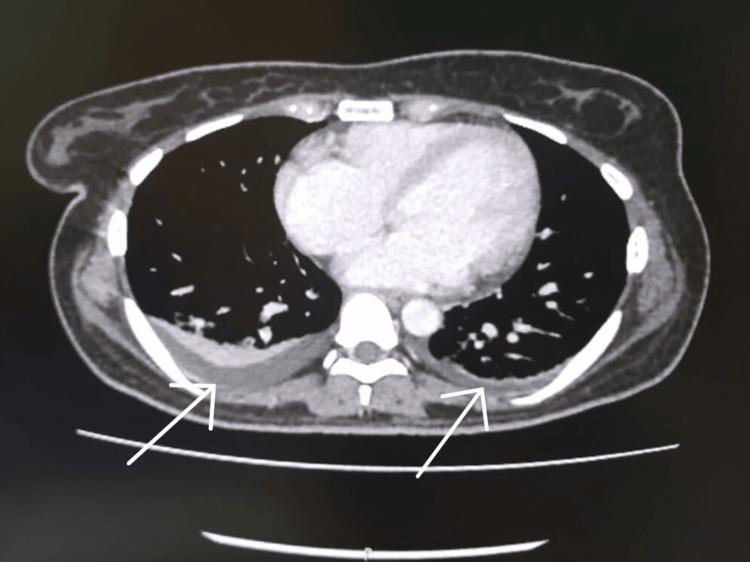

Hemophagocytic lymphohistiocytosis (HLH) is a severe life-threatening hematological disorder characterized by the dysregulation of the immune system and a hyperinflammatory response. Prompt treatment is crucial to prevent fatality. Although primarily affecting infants, HLH can also occur in children and adults. It is classified as primary and secondary, with primary HLH being genetic and predominantly affecting children. Secondary HLH is triggered by infections, malignancy, metabolic disorders, and rheumatological conditions. Diagnosis is based on the HLH-2004 criteria, considering clinical and laboratory parameters. Early diagnosis and treatment improve prognosis. Treatment follows the HLH-94 and HLH-2004 protocol and consists of eight weeks of induction therapy with cyclosporine, corticosteroids, and etoposide. This case describes a 26-year-old female diagnosed with HLH and successfully treated according to the protocol. The patient exhibited improvement and was discharged, demonstrating the importance of early diagnosis and appropriate management in adult HLH cases.

噬血细胞性淋巴组织细胞增生症(HLH)是一种严重的、危及生命的血液系统疾病,其特征为免疫系统失调和过度炎症反应。及时治疗对于预防死亡至关重要。HLH虽然主要影响婴儿,但也可发生于儿童和成人。它分为原发性和继发性,原发性HLH是遗传性的,主要影响儿童。继发性HLH由感染、恶性肿瘤、代谢紊乱和风湿性疾病引发。诊断基于HLH-2004标准,综合考虑临床和实验室参数。早期诊断和治疗可改善预后。治疗遵循HLH-94和HLH-2004方案,包括为期八周的环孢素、皮质类固醇和依托泊苷诱导治疗。本病例描述了一名26岁女性被诊断为HLH并根据该方案成功治疗。患者病情好转并出院,证明了成人HLH病例早期诊断和适当管理的重要性。